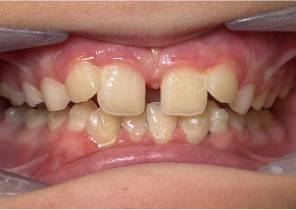

Informe de caso 2

7 años, 11 meses de edad, 24 etapas con dispositivos Invisalign Palatal Expander

Cortesía del Dr. David R. Boschken

Antes de la disyunción con el sistema Invisalign Palatal Expander

Después de la disyunción con el sistema Invisalign Palatal Expander

Después del tratamiento con el sistema Invisalign Palatal Expander